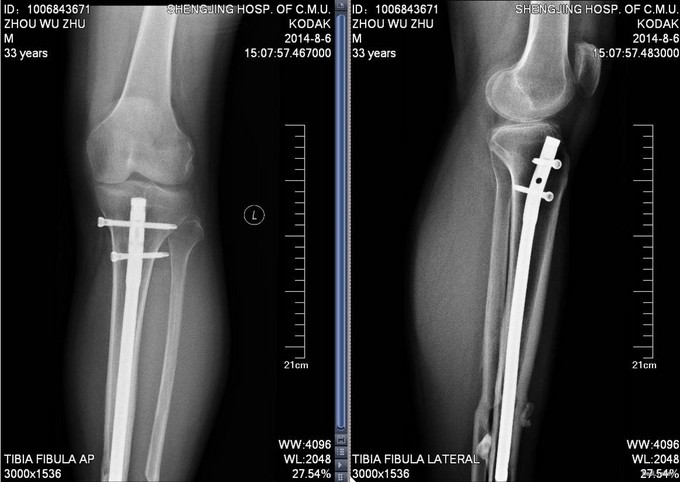

患者2012年8月发生车祸,致右股骨及左胫骨骨折,后于我院行右股骨骨折闭合复位内固定术,左胫骨骨折闭合复位内固定术,手术顺利,安返病房,术后康复锻炼,定期复查,近期复出X线,提示骨折愈合良好,今日门诊以“右股骨骨折,左胫骨骨折术后”为主要诊断收入我科

患者步入病房,神志清,右大腿压痛叩击痛(—),左小腿压痛叩击痛(—)。双下肢等长。双下肢感觉运动均正常。

入院后完善检查,查无手术禁忌症后右股骨干骨折术后内固定物取出术,左胫骨骨折术后内固定物出去术,术后第二天自动退院。